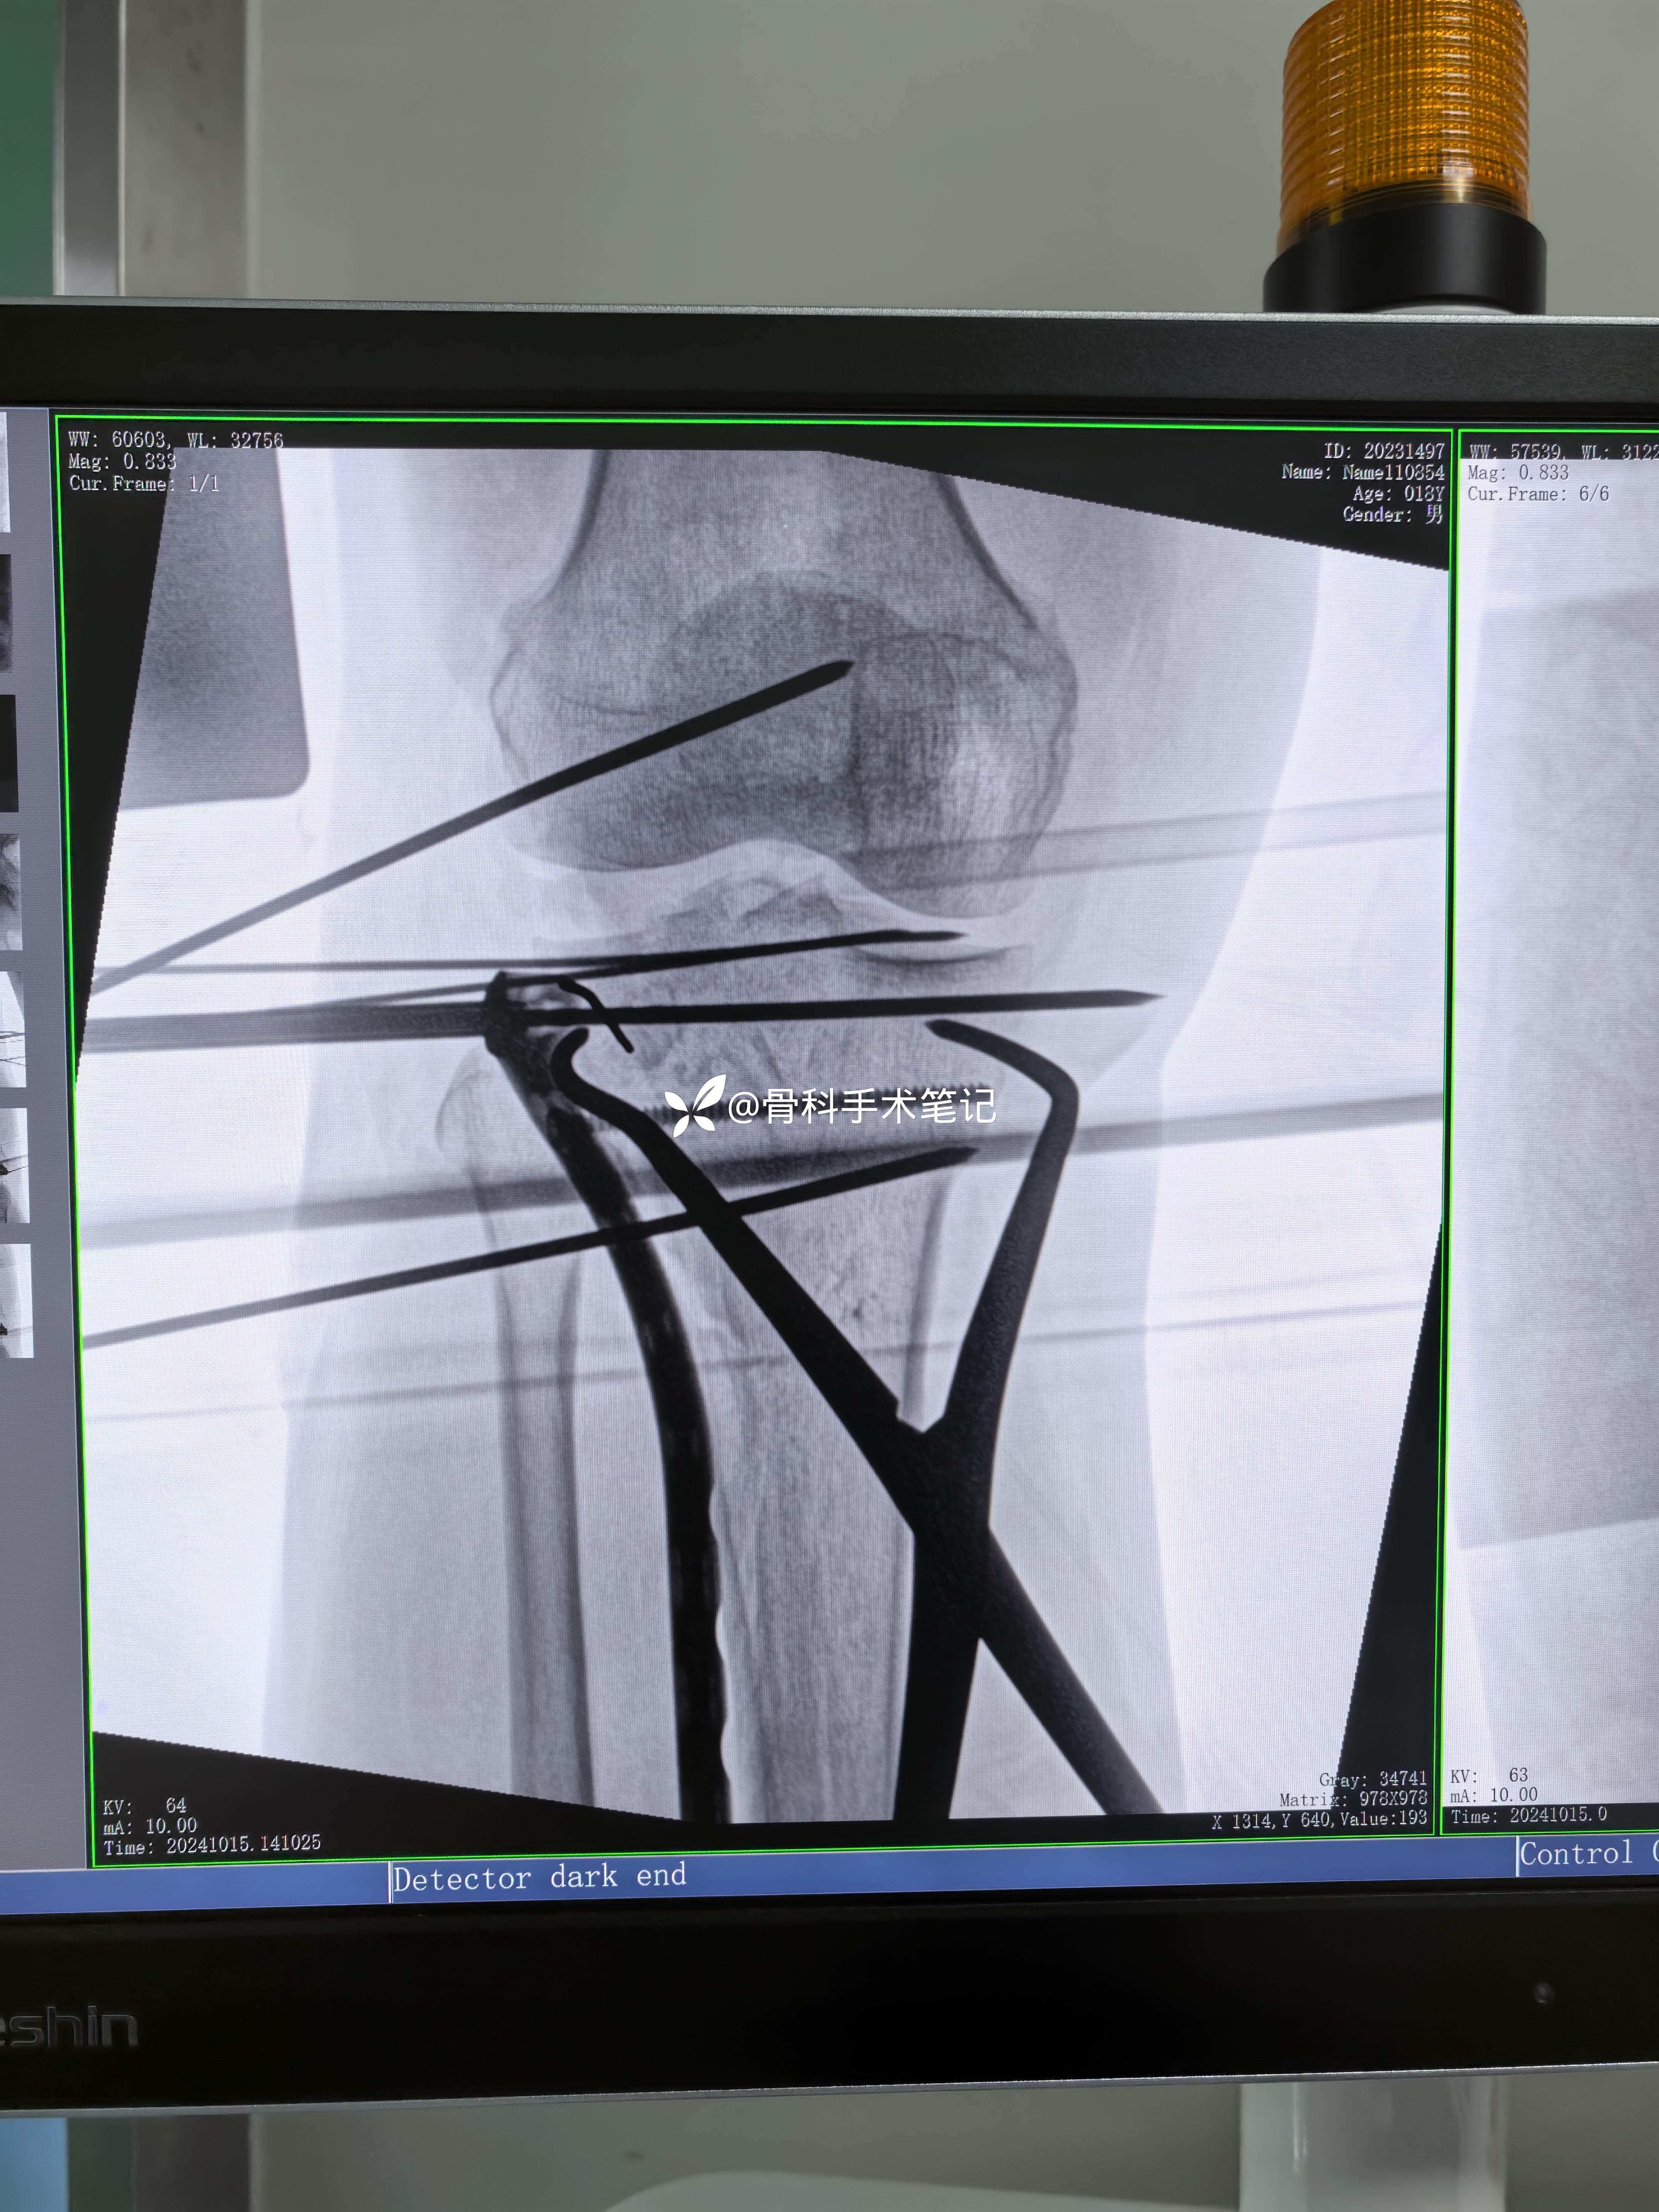

外侧切口→撑开器撑开→缝合修复外侧半月板→外侧开窗复位塌陷的关节骨块克氏针临时固定这→取髂骨植骨支撑→外侧排钉钢板固定。

保留固定关节面骨块克氏针是否会更好呢!